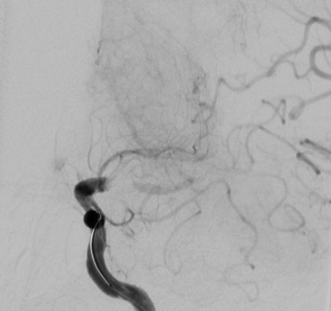

DSA:

患者10天前无明显诱因出现言语不能,部分理解他人的问话,言语少,不能被理解,右侧肢体力弱,可在他人搀扶下行走,后逐渐不能活动。于当地医院完善颅脑MRI+MRA:左侧大脑半球多发急性脑梗死灶;左侧大脑中动脉闭塞;左侧颈内动脉狭窄。完善脑血管造影检查:左侧颈内动脉末端闭塞,以远血管未见显影;后交通动脉及前交通动脉开放,部分代偿左侧颈内动脉供血区供血,余颅内其他脑血管管腔通畅,未见明显异常。于左侧颈内动脉末端行取栓及吸栓,取出及吸出一块黑色血栓,造影显示左侧颈内动脉末端仍闭塞,再次给予吸栓、取栓未见血栓。造影显示左侧颈内动脉末端仍存在充盈缺损且远端血管部分显影,血管床较前增多。局部给予缓慢推注替罗非班注射液25ml,术后给予替罗非班泵入2天治疗,后改为阿司匹林抗血小板治疗。给予瑞舒伐他汀、甘露醇等治疗。6天前肺动脉CTA提示右肺下叶肺动脉栓塞,给予那屈肝素抗凝治疗,同时停用抗板治疗。同时予以转院。